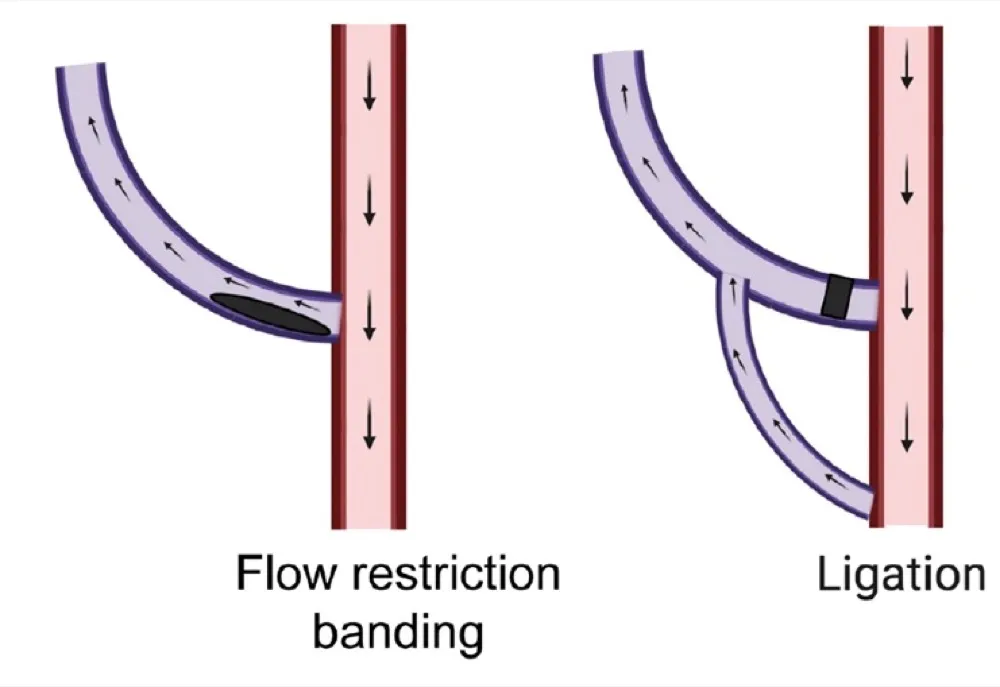

Gestão do Fluxo da Fístula AV: Consulta com cirurgia vascular para avaliação de uma possível intervenção para reduzir o fluxo da fístula.

A intervenções possíveis são: Bandagem de precisão ou fechamento da FAV.

Guardamos o fechamento da FAV para casos de refratariedade